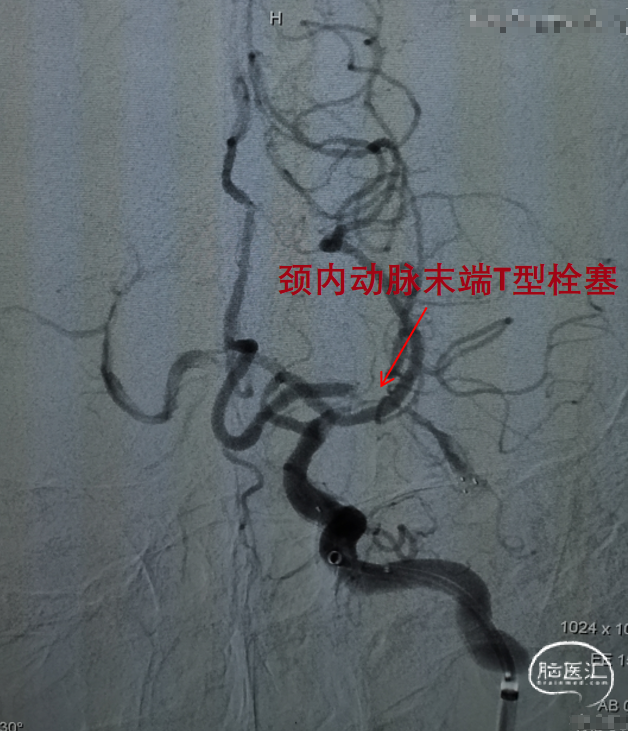

左侧颈动脉造影提示左侧颈内动脉末端闭塞。

置入一枚5*30mm 取栓支架造影。

充盈BGC球囊抽拉结合取栓一次。